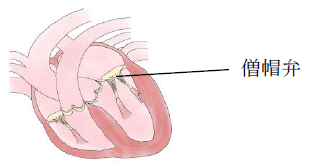

心エコー検査やレントゲン検査など、一通りの心臓の検査を行ったところ、心臓の中にある僧帽弁という扉が上手く閉まっていないと分かりました。

僧帽弁閉鎖不全症(そうぼうべんへいさふぜんしょう)という病名で、犬に最も多い心臓病です。